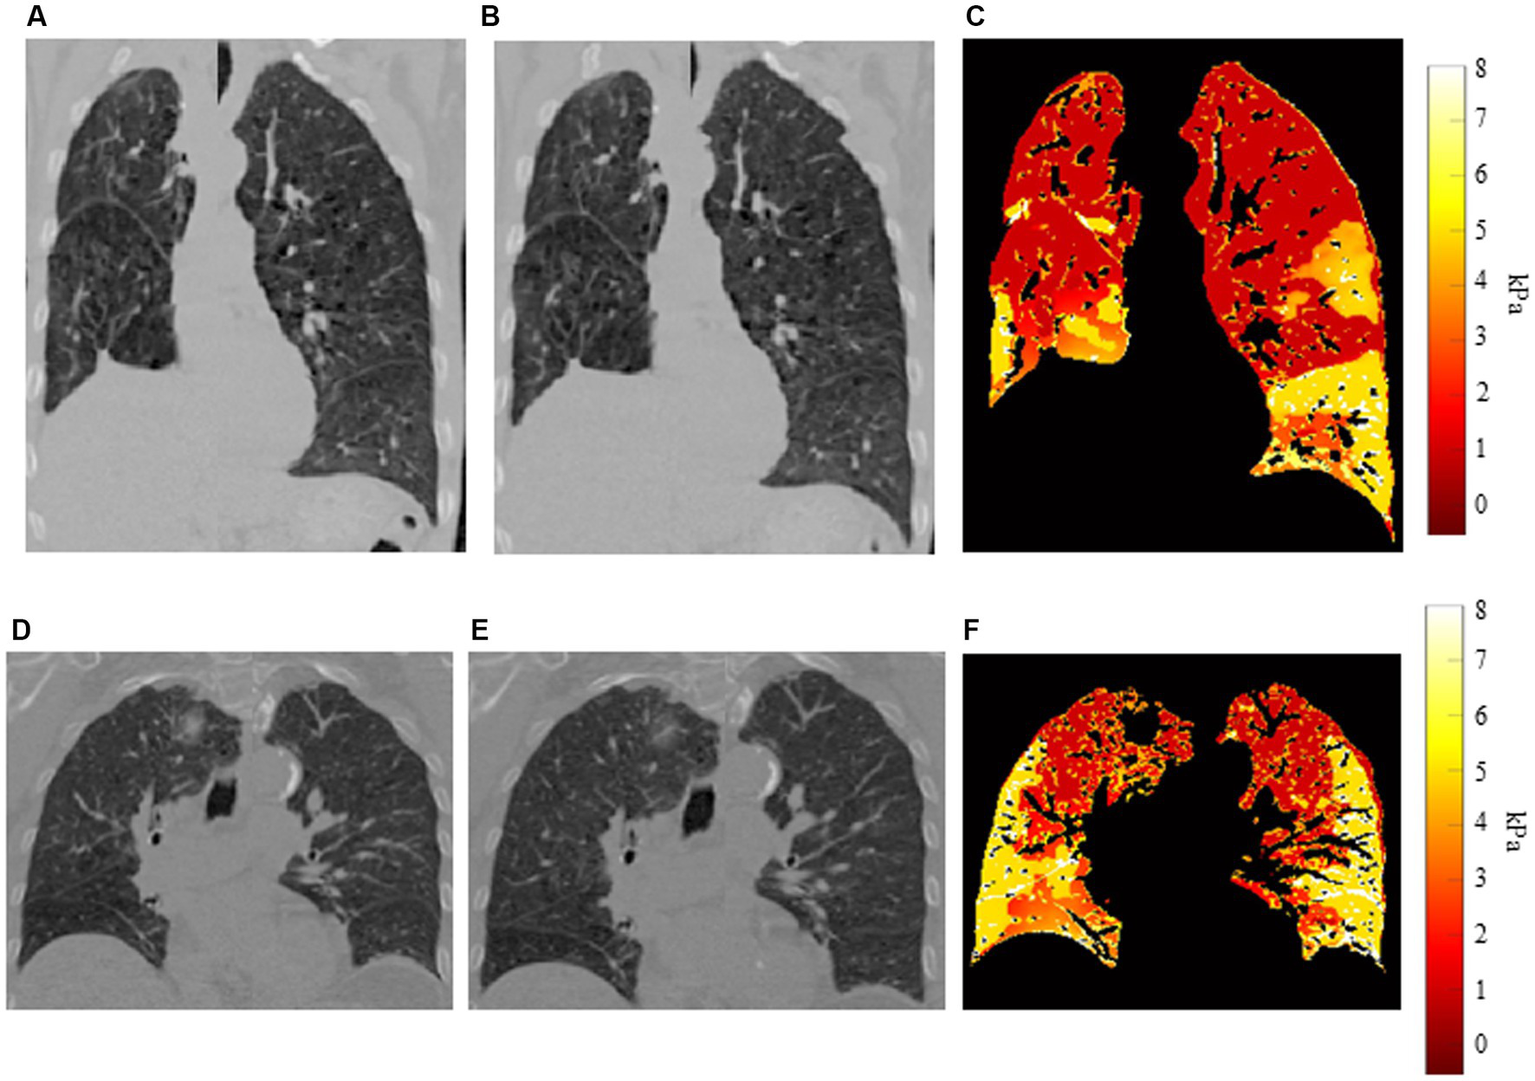

Figure 3 shows examples of our results for two patients. Figures 3A,B show coronal slices of the end-exhalation and end-inhalation scans, respectively, for the patient with high interlobar heterogeneity (EHI = 0.560). The pronounced elasticity difference between the left upper and left lower lobes is apparent in the elasticity distribution shown in Figure 3C. Figures 3D,E show the end-exhalation and end-inhalation scans for a patient with lower interlobar heterogeneity (EHI = 0.248). Regions of high and low elasticity are more dispersed throughout the lobes in this case.

Example distributions for two patients (A) End-exhalation scan, (B) end-inhalation scan, and (C) elasticity distribution for patient with high interlobar heterogeneity. (D) End-exhalation scan, (E) end-inhalation scan, and (F) elasticity distribution for patient with low interlobar heterogeneity.